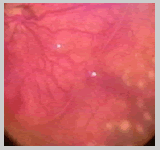

PROLIFERACIÓN NEOVASCULAR PLANA:

En la enfermedad clásica la proliferación neovascular

se produce sobre el ridge y se extiende luego hacia el vítreo,

sin embargo en la ROP en zona I la neovascularización se

produce en el plano de la retina. Clínicamente observaremos

la neovascularización como un color rosado o rojizo en la

retina periférica vascular cercano al limite con la retina

avascular (Foto A) o como pequeños focos de neovascularización

sobre la retina vascular (Foto B).